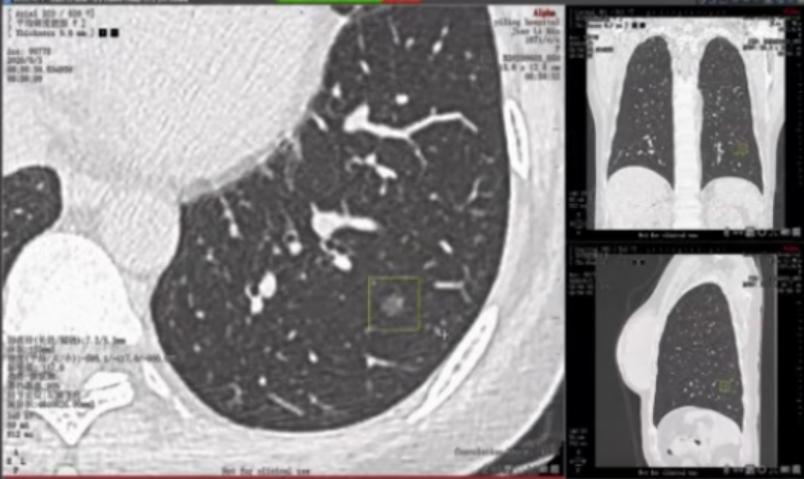

患者术后病例分期为Ia期,但考虑到患者存在双肺结节,复发可能性依然存在。于是患者进入了临床研究,接受了表观遗传学的检测。

结果显示患者复发可能性大,经充分沟通后家属同意加强术后管理(远离雾霾以及烟草污染),术后6月复查薄层CT并进行AI评估。目前患者恢复较好,无复发征象。

我们回顾这一病例可以发现,该患者两次影像学检查均处于相当早期,当没有太多经验的影像科医生或呼吸内科医生面对这一病例时,可能并不能确定结节的良恶性,而建议患者等待观察治疗。

这种等待却在无意间延误了患者的诊断和治疗,使得预后更差、预期寿命更短。而AI集合了经验丰富医生的宝贵临床见识并累加了他们的读图能力,做到了早期识别和确认,让患者得到了早期治疗。